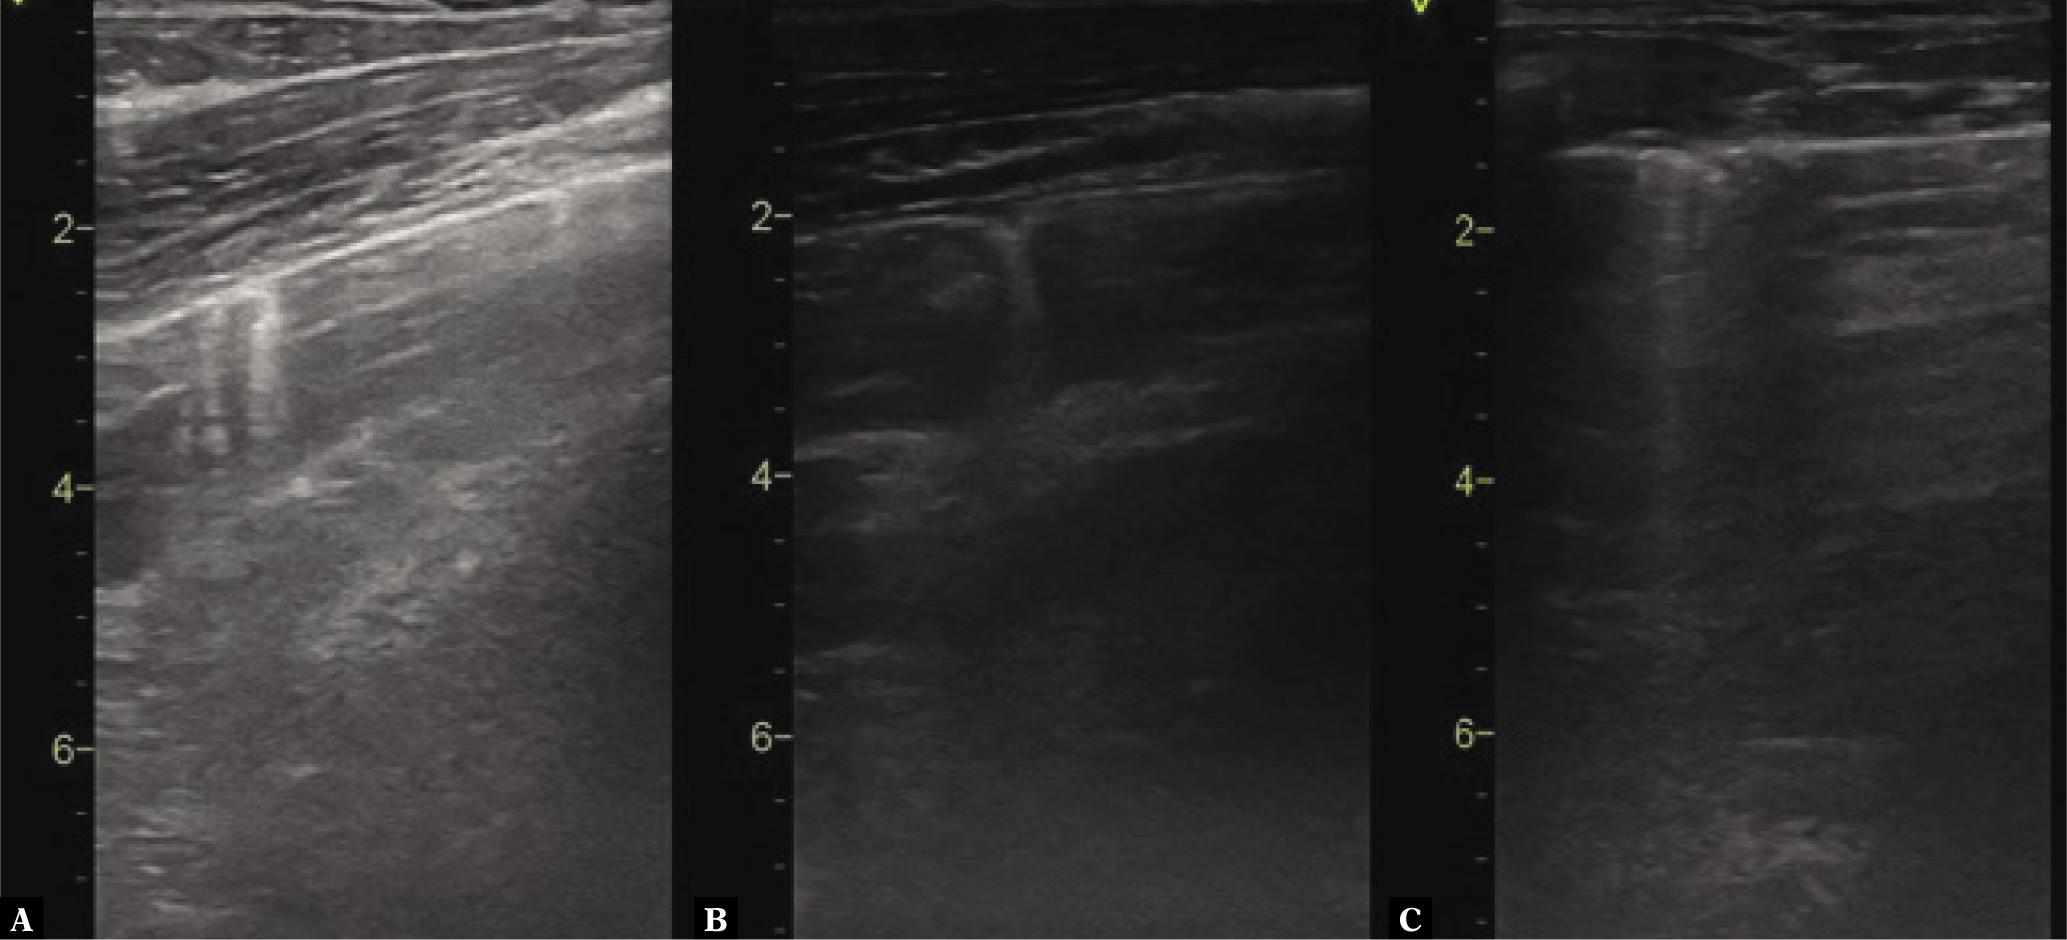

Fig. 3.

Pattern of changes visible on LUS

| Number of patients with dominant “abnormal” pattern* | 7 (22.6%) | 0 (0%) | 3 (17.6%) | 3 (33.3%) | 1 (100%) |

| 1) Big consolidations with thick C-line | 25 | 2 | 12 | 10 | 1 |

| 2) Small consolidations | 45 | 6 | 24 | 14 | 1 |